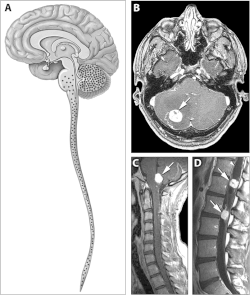

Locations of the main types of cysts and tumors in Von Hippel–Lindau disease.[2]

Typical distribution of hemangioblastomas in Von Hippel–Lindau disease.